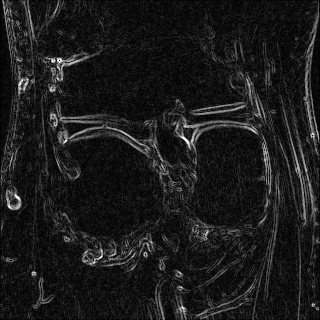

Edge preserving has always been a crucial concern in the design of reconstruction models. To improve the quality of reconstructed images and preserve image edges, some works suggested introducing edge priors in the original restoration problem to preserve image edges [4, 34]. However, they will suffer from complicated algorithm design and time-consuming training processes. Recently, some more efficient methods have been proposed to use edge maps as external guidance for image restoration. For example, Yang et al. [48] used off-the-shelf edge detectors to extract image edges from the degraded images. Fang et al. [12] predicted image edges by constructing an edge reconstruction network. Huang et al. [18] designed a novel dual discriminator GAN framework for solving fast multi-channel MRI, in which one GAN network is built for edge information enhancement. Inspired by these methods, we also consider introducing image edge prior as external guidance to MRI reconstruction since 1) image edges are prominent and distinguishable features in MRI (see Fig. 1), which can serve as a good guide to the model to recover high-frequency details; 2) the ground truth edges can be easily fetched via ordinary edge extraction operators, like Canny, Sobel, and Prewitt, which means that the edge maps can be learned in a data-driven manner. However, how to effectively utilize image edge priors to guide image reconstruction still remains a challenge. In some methods, edge information was simply concatenated with the input image and passed to the next stages. Though this is a simple way to utilize the edge priors, it may not give full play to the guiding role of the edge priors. Therefore, in this work, we want to explore a more efficient and effective mechanism to fully take advantage of image edge priors.

(a)

(b)

(c)

fastMRI is a large-scale MR dataset jointly established by Facebook AI Research and NYU Langone Health. It provides both knee and brain datasets for evaluation. In our work, we use the multi-coil knee dataset, which was acquired on three clinical 3T systems or one clinical 1.5T system using a 15-channel knee coil array. The dataset includes data from two pulse sequences, yielding coronal proton-density weighting with (PDFS) and without (PD) fat suppression. As is shown in Fig. 1, PD images usually contain more structural and prominent edge features than PDFS images, which suggests that it is more challenging to use edge guidance on PDFS datasets. Therefore, we explore the effectiveness of EAMRI on these two modalities. Following [13], for both PD and PDFS knee datasets, we separately filter out 227 volumes (8332 slices) for training and 24 volumes (1665 slices) for testing. The dataset is centrally cropped to .